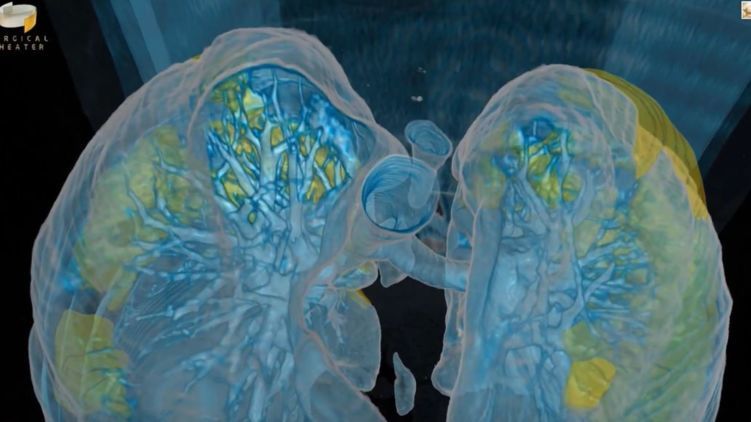

"После перенесенной коронавирусной инфекции в легких наблюдаются фиброзные изменения, как после других воспалительных заболеваний легких. Это бывает после тяжелой пневмонии, при часто обостряющейся хронической обструктивной болезни легких, при интерстициальных заболеваниях легких. У людей идут структурные изменения, которые требуют длительного восстановления", - сказал он.

"Дыхательная гимнастика и укрепляющий режим не противопоказаны и их можно проводить, но все будет зависеть от индивидуальной способности каждого человека, который переболел Covid-19, к структурному восстановлению поврежденного органа. Как это улучшать? Это только само со временем может случиться. После перенесенного свиного гриппа N1H1 наблюдались фиброзные поражения, которые продолжались на протяжении полутора-двух лет. У некоторых легкие не восстановились до сих пор", - подчеркнул он.